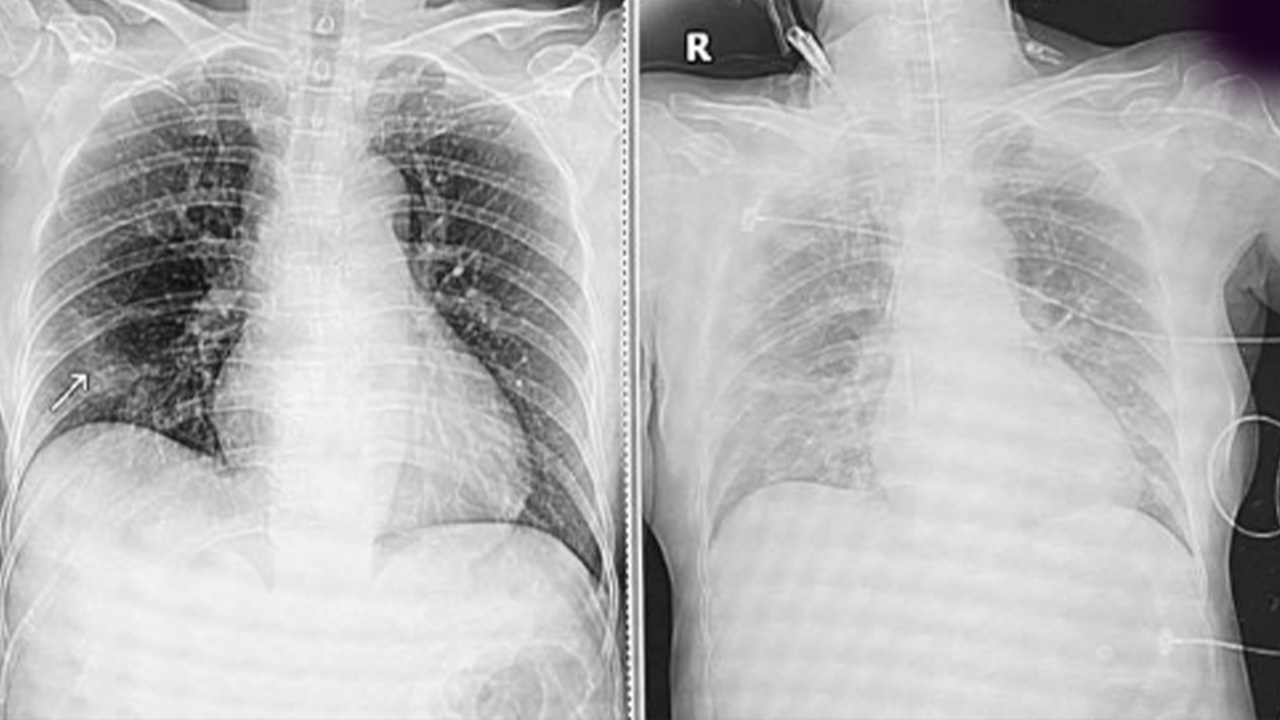

วันที่มาตรวจ คุณป้ามีอาการคล้ายเป็นหวัดมา 6 วัน เอกซเรย์ปอดยังปกติ อีกวันถัดมาอาการปอดอักเสบชัดขึ้น คนไข้หายใจเหนื่อย จนระบบหายใจล้มเหลวอย่างรวดเร็ว ต้องใส่ท่อช่วยหายใจ ย้ายเข้าห้องไอซียู เนื่องจากอาการหนัก เข้าใจความรู้สึกของลูกที่รู้ทีหลังว่าแม่ตัวเองต้องมานอนไอซียูเพราะไม่ระวังเรื่องการกักตัว